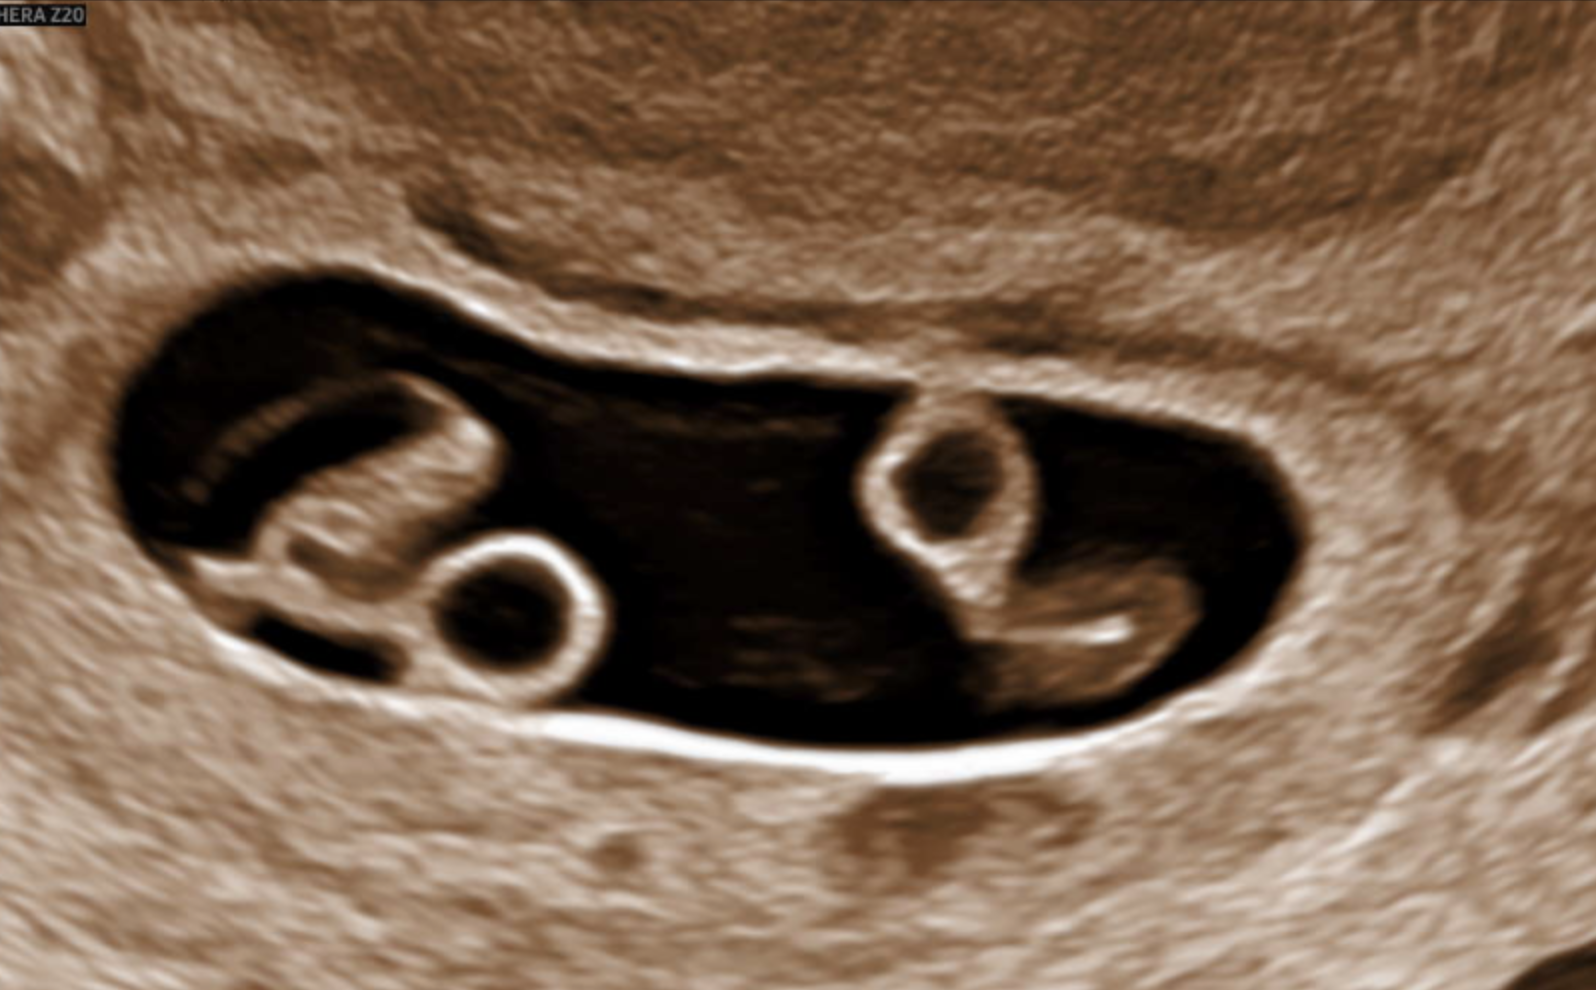

Twins US - can't tell if identical or fraternal?

This is my US at 6w5d and the doctor says she still can't tell if it's identical or fraternal twins. Anyone else get an ultrasound this early and they weren't able to tell if identical or fraternal? Just curious.